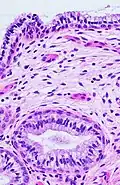

The endocervical mucosa is about 3 mm (0.12 in) thick and lined with a single layer of columnar mucous cells. It contains numerous tubular mucous glands, which empty viscous alkaline mucus into the lumen.[4] In contrast, the ectocervix is covered with nonkeratinized stratified squamous epithelium,[4] which resembles the squamous epithelium lining the vagina.[17]: 41 The junction between these two types of epithelia is called the squamocolumnar junction.[17]: 408–11 Underlying both types of epithelium is a tough layer of collagen.[18] The mucosa of the endocervix is not shed during menstruation. The cervix has more fibrous tissue, including collagen and elastin, than the rest of the uterus.[4]

The squamocolumnar junction of the cervix, with abrupt transition: The ectocervix, with its stratified squamous epithelium, is visible on the left. Simple columnar epithelium, typical of the endocervix, is visible on the right. A layer of connective tissue is visible under both types of epithelium. -

In prepubertal girls, the functional squamocolumnar junction is just within the cervical canal.[17]: 411 Upon entering puberty, due to hormonal influence, and during pregnancy, the columnar epithelium extends outward over the ectocervix as the cervix everts.[15]: 106 Hence, this also causes the squamocolumnar junction to move outwards onto the vaginal portion of the cervix, where it is exposed to the acidic vaginal environment.[15]: 106 [17]: 411 The exposed columnar epithelium can undergo physiological metaplasia and change to tougher metaplastic squamous epithelium in days or weeks,[17]: 25 which is very similar to the original squamous epithelium when mature.[17]: 411 The new squamocolumnar junction is therefore internal to the original squamocolumnar junction, and the zone of unstable epithelium between the two junctions is called the transformation zone of the cervix.[17]: 411 Histologically, the transformation zone is generally defined as surface squamous epithelium with surface columnar epithelium or stromal glands/crypts, or both.[20]